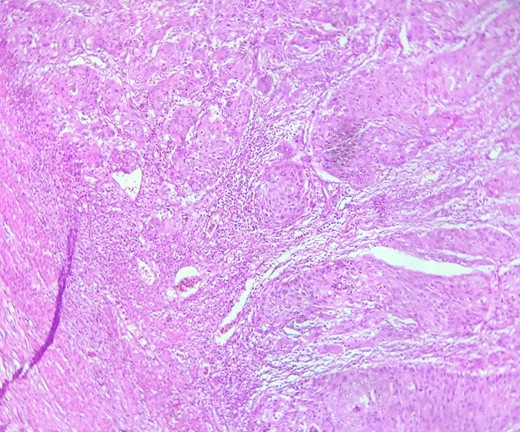

Mr. A. is a 65-year-old hypertensive patient presenting with acute epigastric pain associated with abdominal bloating. Biological settings showed amylasemia at 450 IU/L and lipasemia at 525 IU/L. Abdominal CT scan revealed heterogenous poorly defined mass in the pancreatic head with low enhancement (Figs 1 and 2). The CA 19–9 assay was 280 IU/L. Cephalic duodenopancreatectomy was performed. Histological examination of the operative specimen revealed a solid, trabecular, undifferentiated carcinomatous process (Fig. 3) expressing markers (CK(AE1-AE3) and p40) (Fig. 4), confirming the diagnosis of primary squamous cell carcinoma of the pancreas. The extension study showed no secondary localization.

HE section: The tumor cells are so poorly differentiated that it is difficult to tell what the cell of origin is. The cells are discohesive with bizarre looking nuclei (×400).